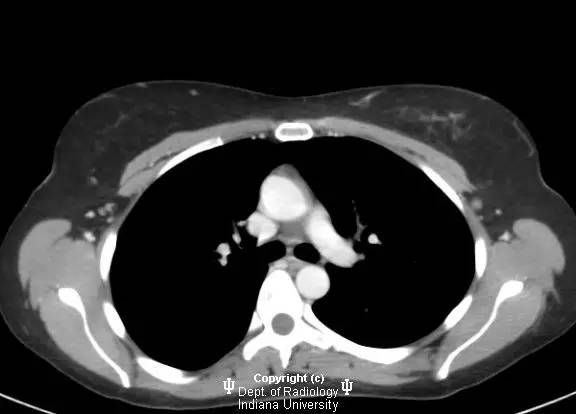

【影像学表现】

乳腺钼靶左乳腺内上象限见3.1cm卵圆形等密度肿块,部分界限清晰。超声见一2.5 x 2.1 x 1.9 cm混合回声肿块,宽大于高,边界清晰,后部回声增强。

浸润性导管癌

Invasive ductalcarcinoma

浸润性导管癌为乳腺癌的最常见类型(80%),有人认为由导管原位癌进展而来,病变可沿着真皮淋巴管播撒而导致皮肤增厚和乳头内陷。肿瘤多无症状,筛查时发现。女性多于中年好发。浸润性导管癌也是男性乳腺癌的最常见类型。淋巴结累及时提示预后不良。诊断多经超声引导下或立体定位活检。局限性病变治疗主要为手术,也可行放疗,化疗和激素治疗。